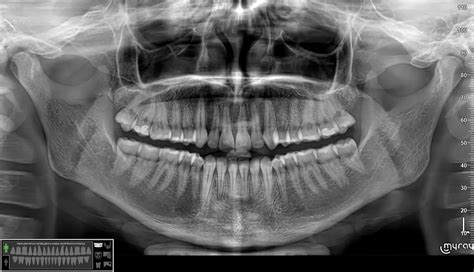

Kaukolės kaulų lūžiams diagnozuoti dažniausiai naudojami vaizdavimo metodai, tokie kaip rentgeno tyrimai, kompiuterinė tomografija (KT) ir magnetinio rezonanso tomografija (MRT). Rentgeno tyrimas gali padėti nustatyti lūžio buvimą, o KT ir MRT leidžia įvertinti smegenų pažeidimus ir aplinkinių audinių būklę.

Įtariant kaulo lūžį, atliekamos 2 krypčių - tiesinės ir šoninės projekcijos rentgenogramos. Sudėtingais atvejais atliekami papildomi radiologiniai tyrimai - įvairių projekcijų rentgenogramos, kompiuterinė tomografija (KT), magnetinio rezonanso tomografija (MRT), kaulų scintigrafija, rentgenoskopija.

- Rentgeno spinduliai sukuria dvimatį lūžio vaizdą.

- Kompiuterinė tomografija naudoja kompiuterius ir rentgeno spindulius, kad sukurtų detalius kaulų pjūvius.

- MRI sukuria labai detalius vaizdus, naudodama stiprius magnetinius laukus.

Rentgenografija yra pagrindinis ir anksčiausiai atliekamas radiologinis tyrimas, įtariant kaulų lūžį. Rentgenogramose dažniausiai vertinami kaulai, tačiau galima gauti naudingos informacijos apie greta esančius minkštuosius audinius. Reikia atlikti bent 2 projekcijų rentgenogramas: tiesinę ir šoninę. Galūnių rentgenogramos dažniausiai apima ir distalinį bei proksimalųjį sąnarius, norint įvertinti galimą jų pažeidimą. Kartais atliekamos įstrižinės projekcijos rentgenogramos, kurios padeda vizualizuoti sudėtingesnės anatomijos sričių, pavyzdžiui, riešo kaulų, pažeidimus. Esant riešo bei pėdos sužalojimams ir vaikams palyginimo tikslu atliekamos ir priešingos pusės rentgenogramos. Jei lūžis įtariamas, bet nesimato rentgenogramose, galima pakartoti tyrimą po 7-10 dienų arba rinktis kitą metodą. Rentgenoskopija dažnai naudojama per operacijas reponuojant ir fiksuojant kaulų lūžius ir dislokacijas.

KT nėra pirmo pasirinkimo tyrimas, ji atliekama vėliau negu rentgenologinis tyrimas, norint sužinoti daugiau apie lūžio fragmentų lokalizaciją. KT atliekamas sudėtingų, komplikuotų lūžių atvejais, tomogramose gerai matomas sąnarių, minkštųjų audinių sužeidimas. Intraveninio kontrastavimo lūžiui įvertinti dažniausiai nereikia, nebent įtariama kraujagyslių, pilvo ar dubens trauma. Metaliniai objektai, tokie kaip kulkos fragmentai ar ortopedinės priemonės gali sumažinti vaizdo kokybę. KT metodas dažniausiai naudojamas riešo, pėdos, kaukolės, stuburo ir dubens lūžiams nustatyti ir charakterizuoti. Retkarčiais nedislokuoti lūžiai nėra lengvai matomi tomogramose.